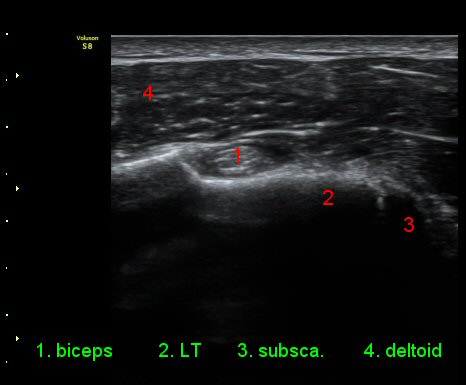

ÀÌµÎ¹Ú±Ù°Ç È¾´Ü¸é°Ë»ç¿¡¼­ °ÇÁÖÀ§¿¡ ¼Ò·®ÀÇ ¼ö¾×Àú·ù¿Í Á¡¾×³¶³» ¾×Àú·ù°¡ °üÂûµÈ´Ù(»çÁø 1, 2).